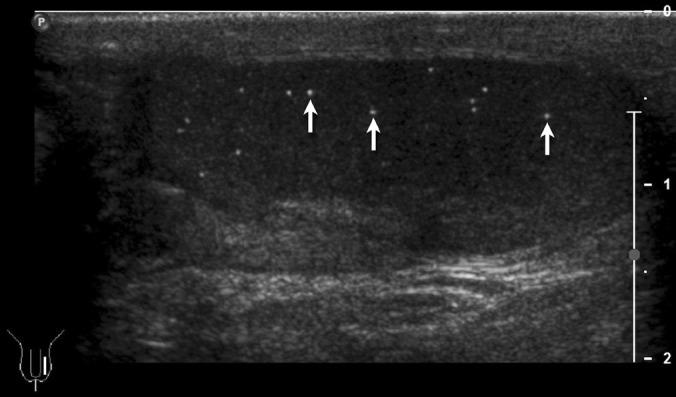

A nine and 13-year-old boy, previously diagnosed with 18q syndrome and an 11q deletion, respectively were diagnosed with testicular microlithiasis (TM). Both cases demonstrate that TM occurs in patients with various chromosomal abnormalities.

一名9岁男孩和一名13岁男孩,之前分别被诊断患有18q综合征和11q缺失,现均被诊断为睾丸微石症(TM)。这两个病例均表明,TM发生于患有各种染色体异常的患者中。